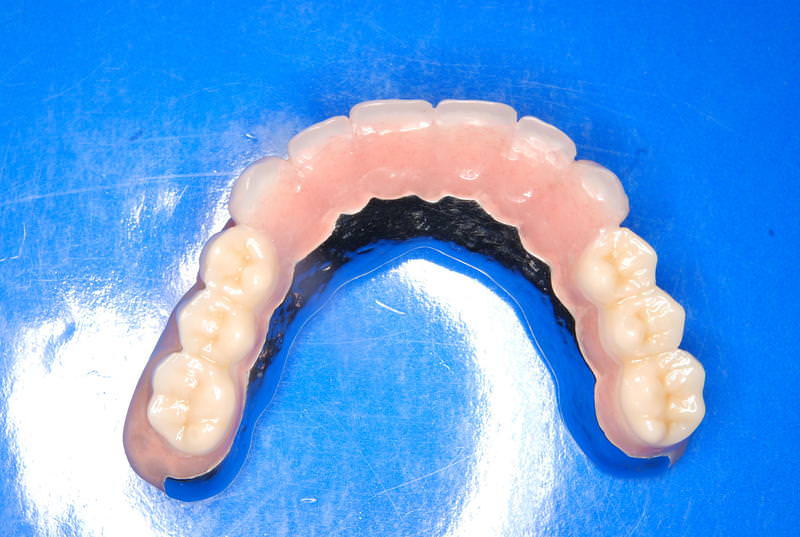

上顎左右臼歯部の4本は、骨の高さが不足していた為、ソケットリフト(骨造成)を採用。免荷期間を経て、ケラターアタッチメントを用いたオーバーデンチャーを装着。人工歯のメタルアップにはジルコニアを選択。